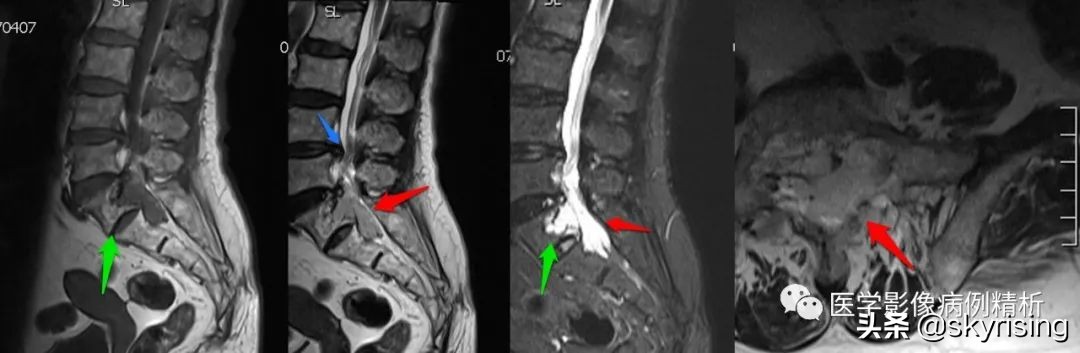

MRI增强

MRI增强对比图

如图所示,分别为T1WI增强矢状位、冠状位、轴位,T1WI增强矢状位与T2WI压脂像非常相像,注意椎管内脑脊液信号,T1WI增强为低信号与T2WI压脂像高信号正好相反。红色箭头所示病灶明显强化,呈亮灯征感觉,清晰显示病灶范围,绿色箭头所示为病灶侵及骶1椎体后缘形成不规则形骨质破坏区。

红色箭头:病灶位于骶1-2椎体水平,轴位呈哑铃型,CT见骶1-2椎体后缘受侵、骨质破坏;MRI见病灶主体沿骶管及双侧骶孔生长,以左侧骶孔为著,T1低信号,T2稍高信号,压脂像高信号,接近脑脊液信号。

绿色箭头:骶1-2椎体后缘见信号向内部侵犯,边缘毛糙。